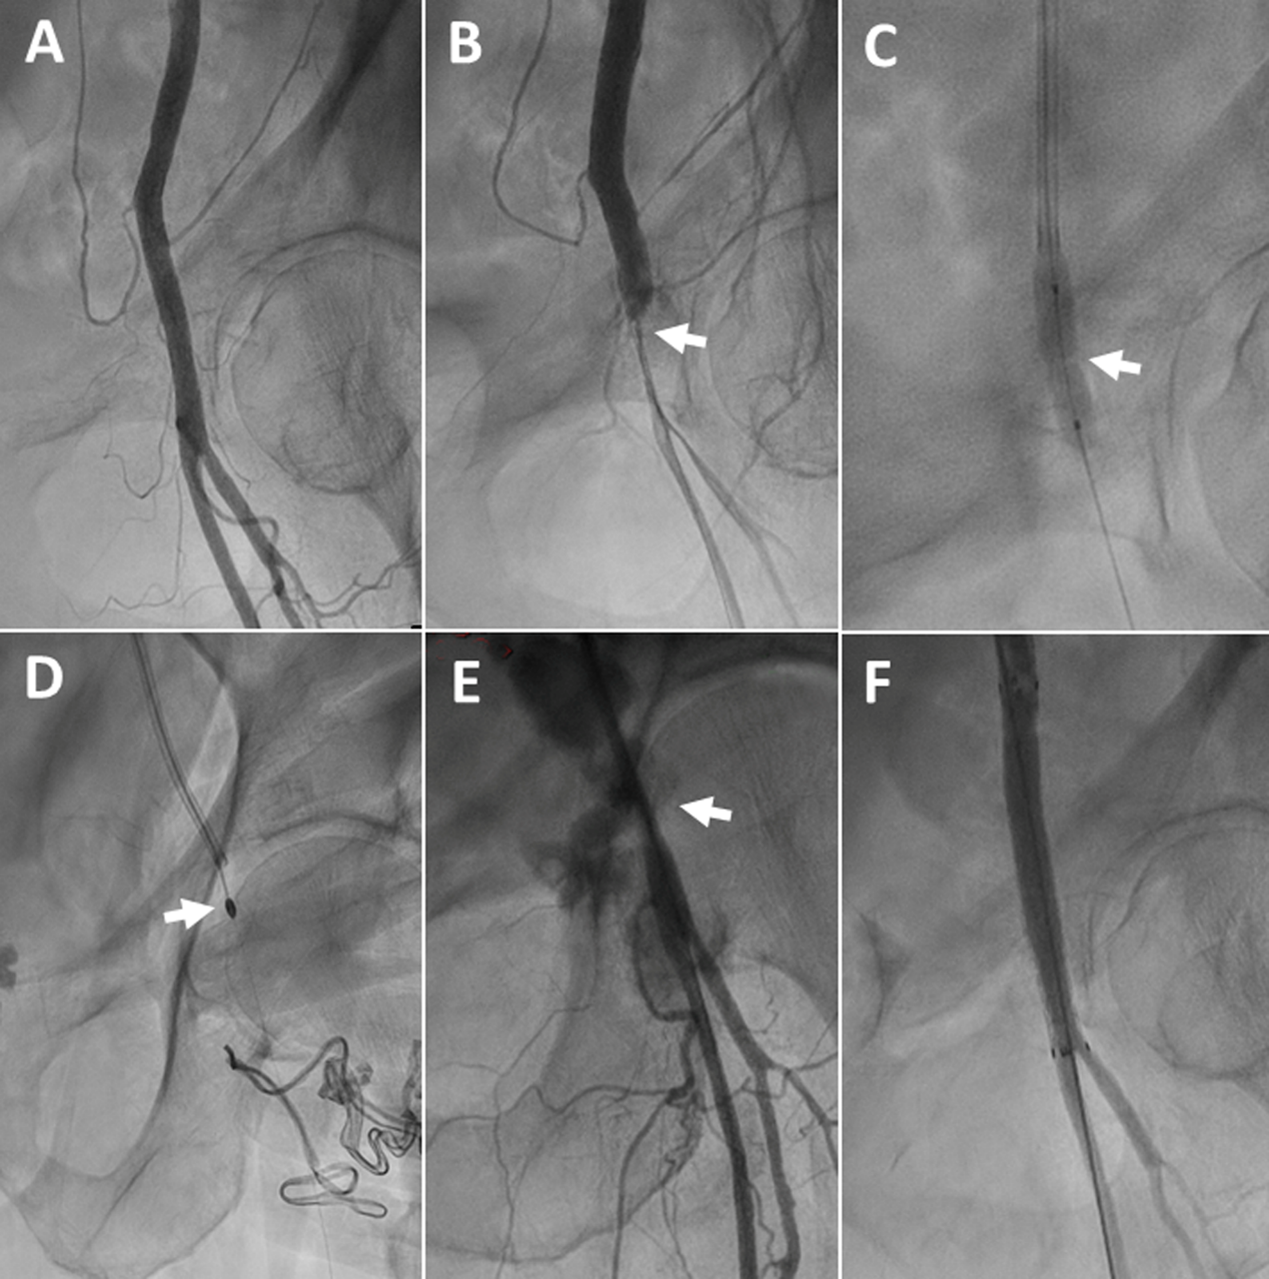

An 88-year-old man with severe symptomatic aortic stenosis (AS), renal failure, and peripheral vascular disease underwent transaxillary TAVR. A 14-French (Fr) sheath was used for the procedure. Following sheath removal, the patient developed a critical stenosis at the access site in the left axillary artery, caused by the sutures of the Perclose ProStyle VCD (Abbott) (Figure 1, Video 1). Balloon dilation failed to dilate the stenosis. The occlusive sutures were ablated using rotational atherectomy via transfemoral access using a 2.0-mm burr (Video 2). Subsequently, an 8 x 60-mm Fluency stent graft (BD) was implanted, and blood flow was restored (Video 3).